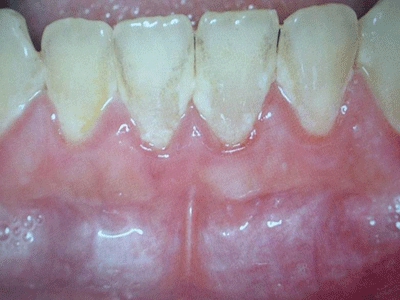

慢性龈炎的病损部位一般局限于游离龈和龈乳头,以前牙区为主,尤其以下前牙区最为显著,患者常因刷牙或咬硬物时牙龈出血而就诊。游离龈和龈乳头颜色变为鲜红或暗红色,病变较重时炎性充血可波及附着龈。龈缘变厚,龈乳头圆钝肥大,可增生呈球状,覆盖牙面。牙龈松软脆弱,缺乏弹性。

龈缘附近牙面上堆积的牙菌斑是引起慢性龈炎的始动因子,其他如牙石、食物嵌塞、不良修复体等均可促使牙菌斑积聚,引发或加重牙龈炎症。